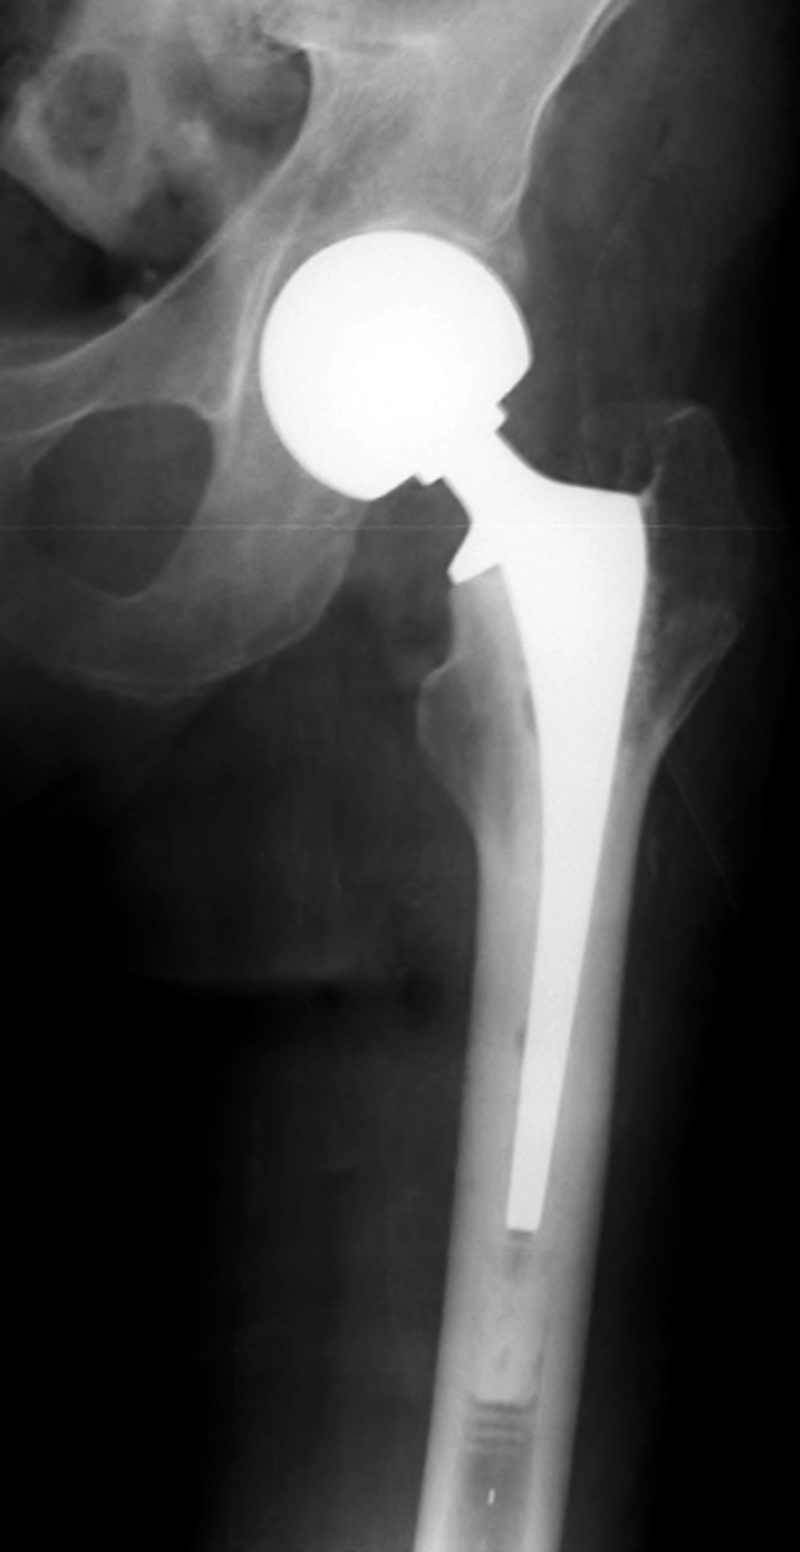

| Total hip arthroplasty with cerclage wires |

| |

The cerclage wires were placed because a femoral shaft fracture (not visible herein) occurred during the prosthesis placement. There is subcutaneous gas from recent placement of the prosthesis. From Taljanovic, 2005 |